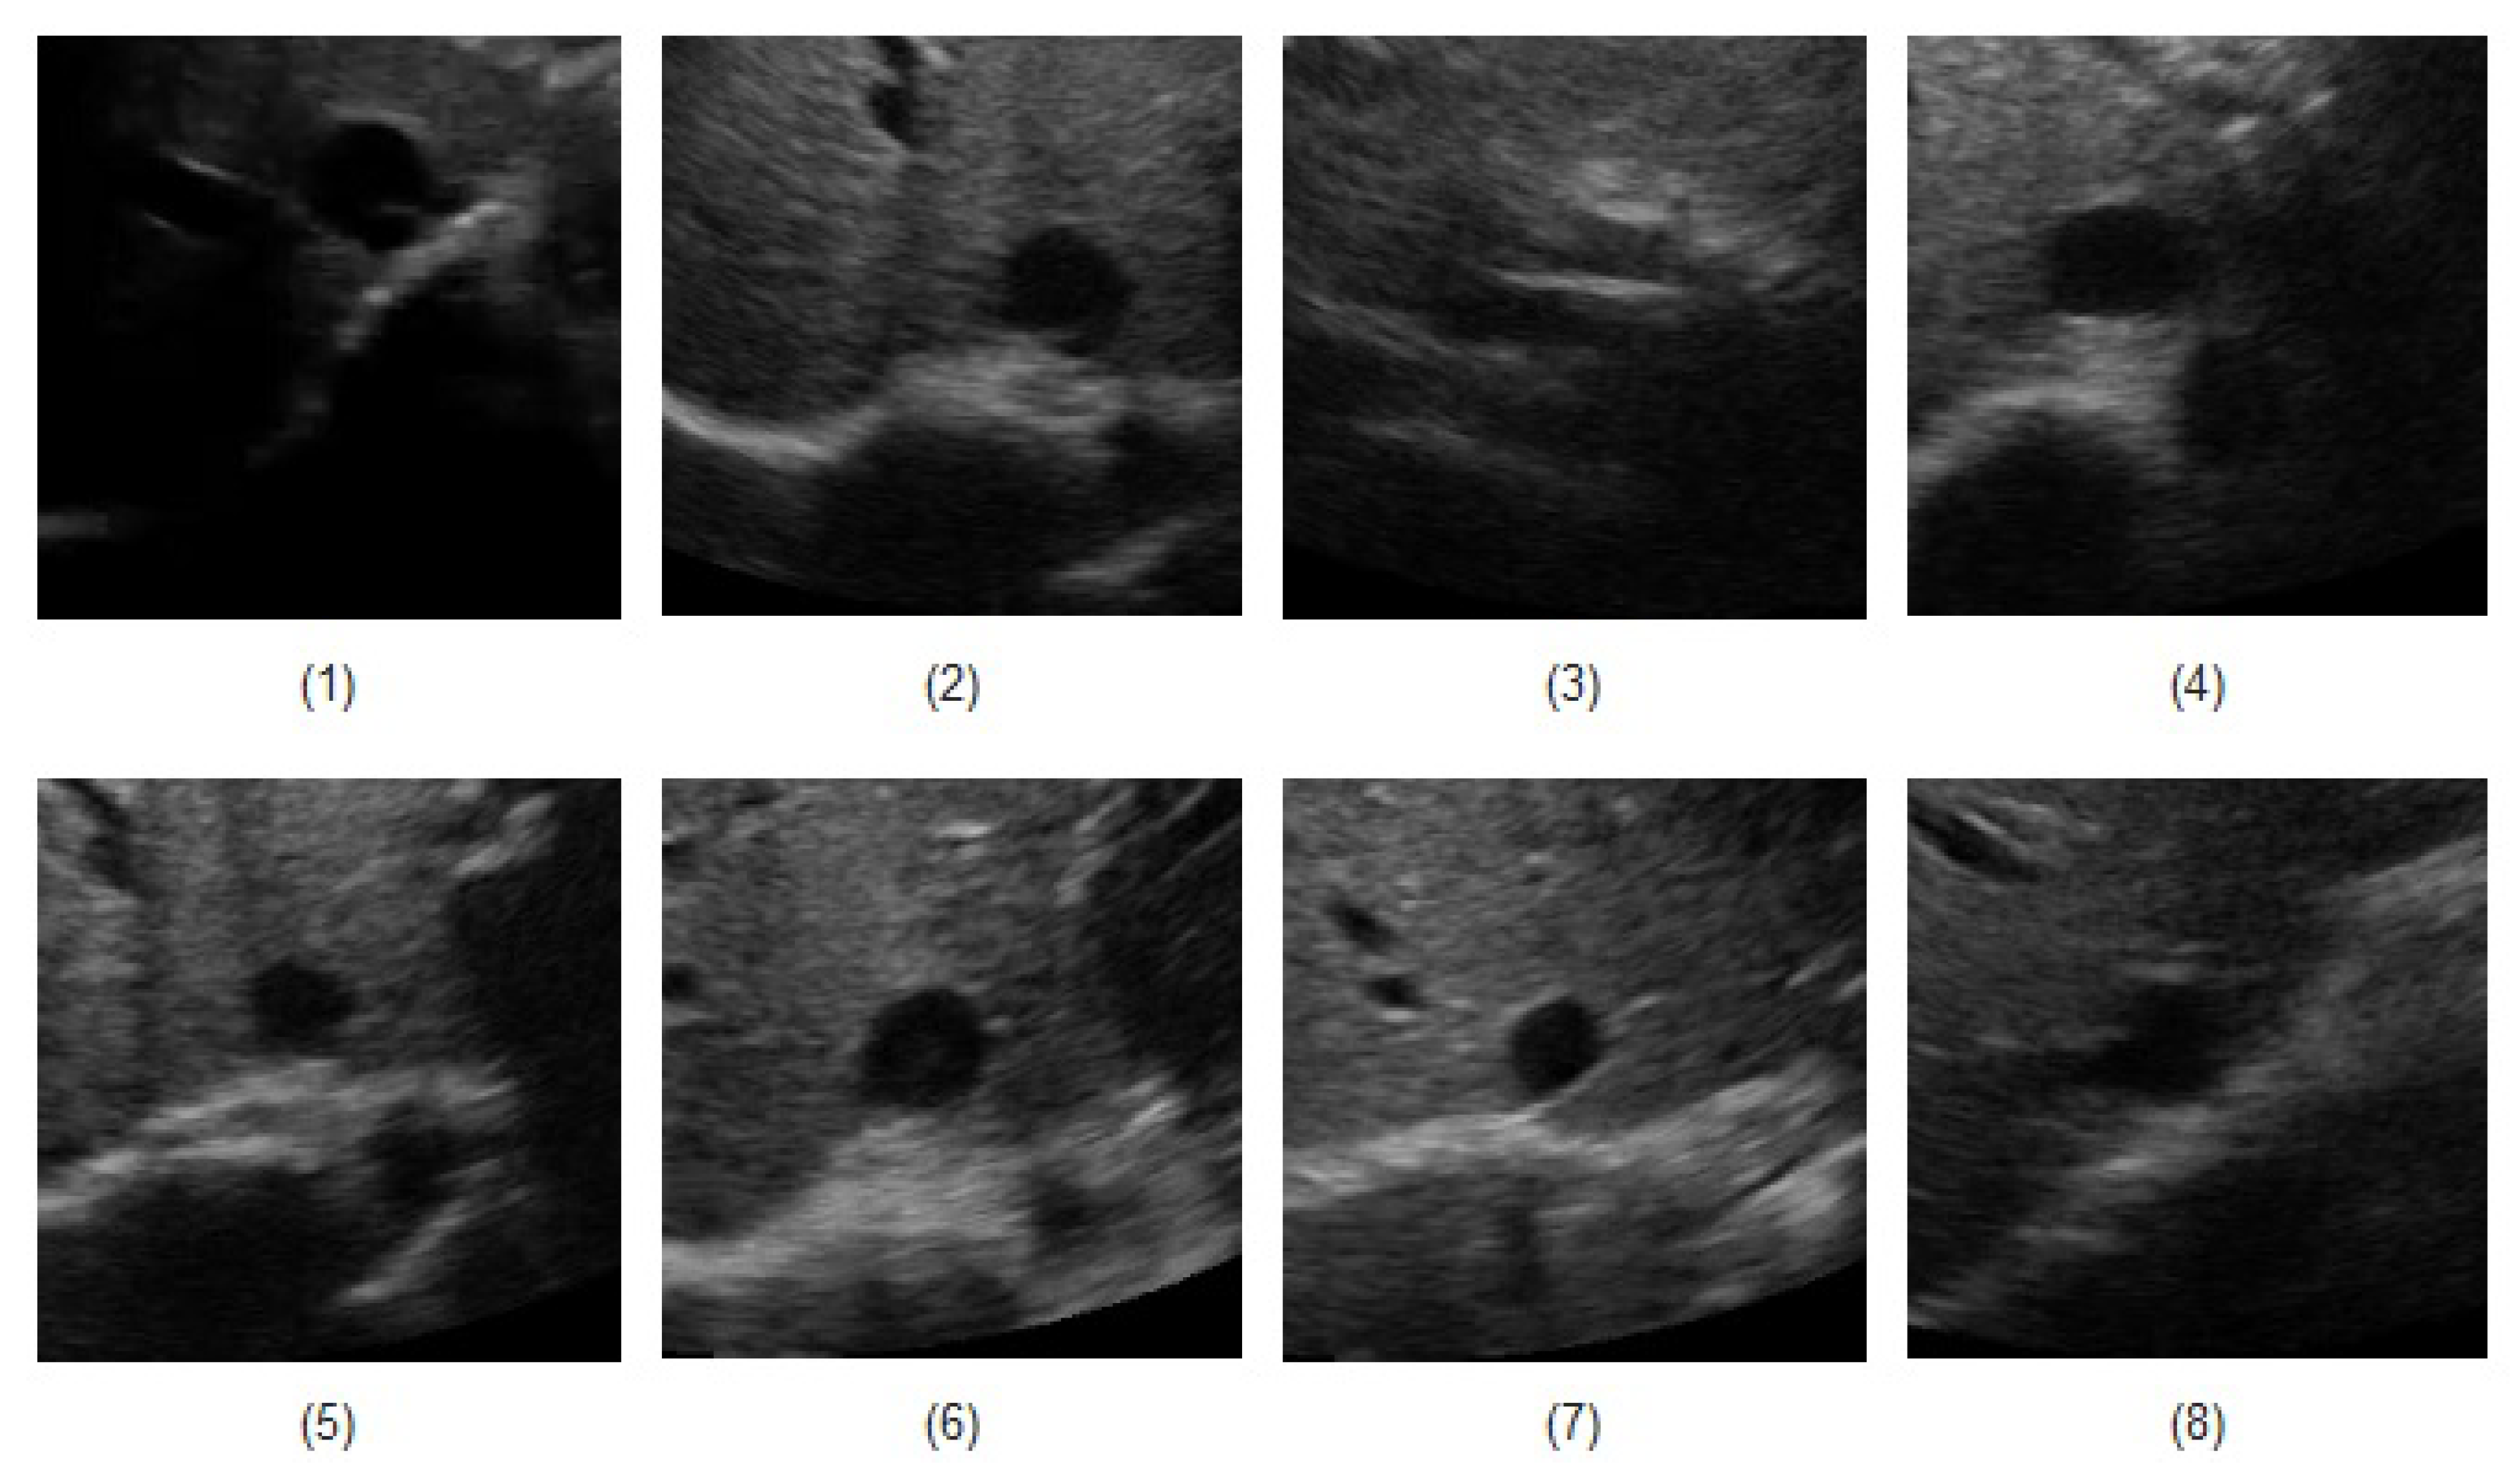

| Subject No. | (1) | (2) | (3) | (4) | (5) | (6) | (7) | (8) | Ave. | |

|---|---|---|---|---|---|---|---|---|---|---|

| Method | ||||||||||

| Circle model | 0.10 | 0.16 | 0.16 | 0.25 | 0.25 | 0.10 | 0.11 | 0.26 | 0.17 | |

| Ellipse model | 0.21 | 0.19 | 0.14 | 0.26 | 0.18 | 0.11 | 0.11 | 0.20 | 0.35 | |

| Rectangle model | 0.08 | 0.11 | 0.12 | 0.23 | 0.14 | 0.10 | 0.10 | 0.18 | 0.12 | |

| Subject No. | (1) | (2) | (3) | (4) | (5) | (6) | (7) | (8) | |

|---|---|---|---|---|---|---|---|---|---|

| Method | |||||||||

| Circle model | 0.06 | 0.29 | 0.48 | 0.57 | 0.75 | 0.41 | 0.44 | 0.43 | |

| Ellipse model | 0.11 | 0.32 | 0.35 | 0.59 | 0.48 | 0.54 | 0.47 | 0.38 | |

| Rectangle model | 0.05 | 0.18 | 0.19 | 0.42 | 0.28 | 0.37 | 0.39 | 0.29 | |